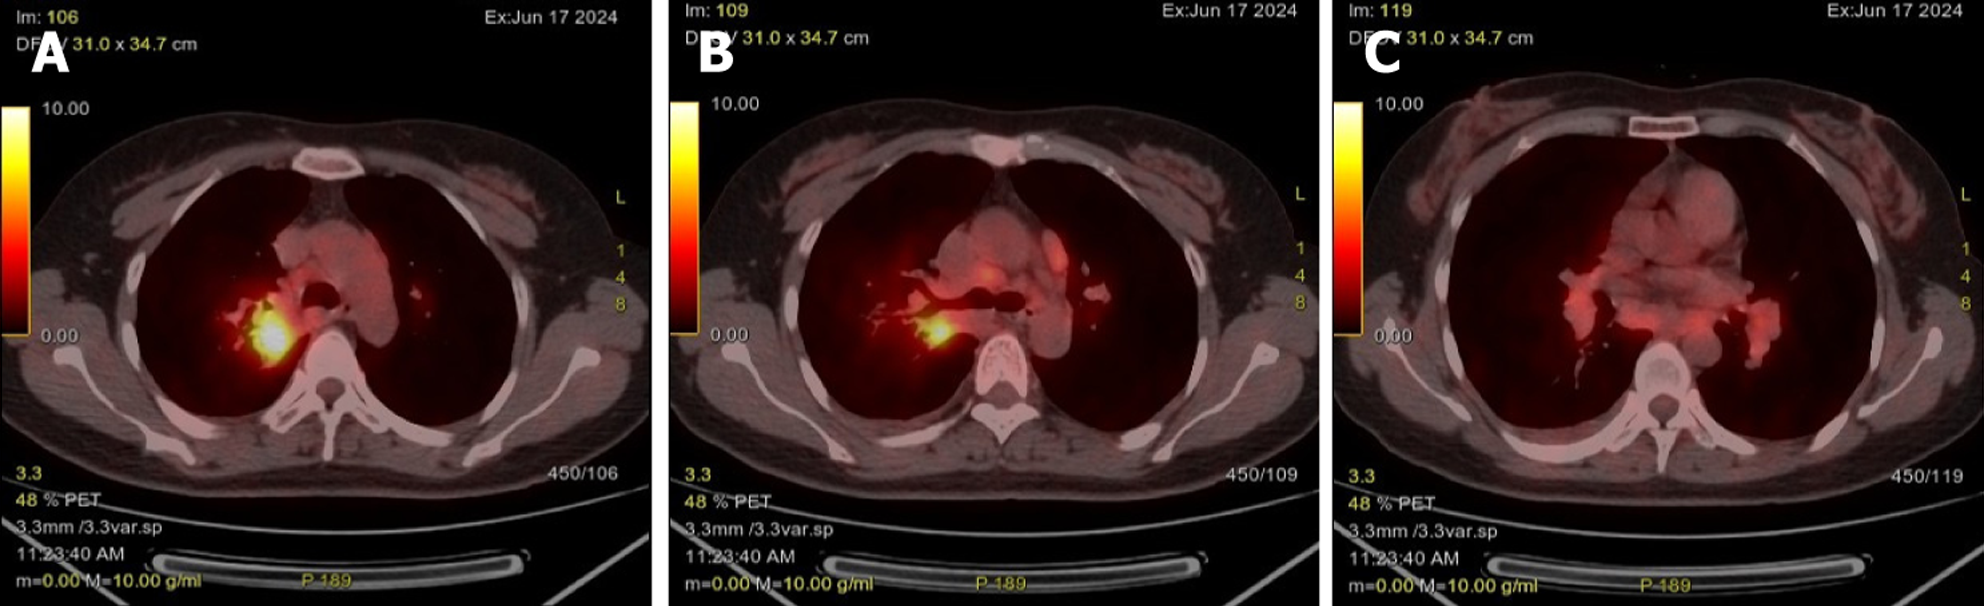

Case 2: Initial contrast-enhanced chest CT at a local hospital revealed multiple enlarged lymph nodes in the right supraclavicular fossa, mediastinum, and bilateral hilar regions (some poorly demarcated from the mid-esophagus), bilateral pulmonary nodules, right bronchial dilation with acute/chronic infection, and localized right pleural thickening (Figure 5). Subsequent PET-CT (December 11, 2024) demonstrated the following symptoms (Figure 6): (1) Widespread hypermetabolic lymphadenopathy (bilateral supraclavicular, mediastinal, hilar, internal mammary, abdominal, and retroperitoneal nodes; SUVmax 8.16; (2) Nasopharyngeal thickening with hypermetabolism; (3) Bilateral hypermetabolic pulmonary consolidations with interstitial changes (prominent in the right upper lobe posterior segment); (4) T11 vertebral focal hypermetabolism (no CT evidence of bone destruction); and (5) Splenomegaly (normal metabolism).

Classic thoracic imaging features include bilateral hilar/mediastinal lymphadenopathy with pulmonary infiltrates. However, atypical radiological findings - as seen in both our cases - pose diagnostic challenges. Case 1 presented with a right upper lobe mass and paratracheal lymphadenopathy mimicking lung cancer with metastases, while case 2 exhibited multiregional hypermetabolic lymphadenopathy and thrombocytopenia, initially suggestive of lymphoma. These scenarios underscore the necessity of integrating clinical, radiological, and histopathological data for accurate diagnosis. Bronchoscopy with bronchoalveolar lavage lymphocyte subset analysis (increased CD4/CD8 ratio) and mediastinal lymph node sampling are pivotal in such ambiguous cases.